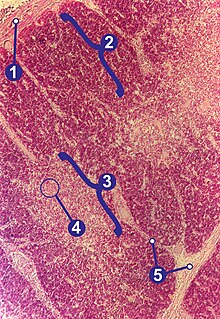

Im Gegensatz zu den übrigen lymphatischen Organen, die ausschließlich aus dem Mesoderm hervorgehen, entwickelt sich der Thymus aus dem Meso-, dem Ento- und dem Ektoderm und wird daher als lymphoepitheliales Organ bezeichnet. Histologisch lassen sich im Thymus Läppchen (Lobuli thymici) mit Rinde und Mark unterscheiden. Besonders im Thymusmark befinden sich beim Menschen und den meisten anderen Wirbeltieren die für das lymphatische Gewebe des Thymus typischen Hassall-Körperchen.